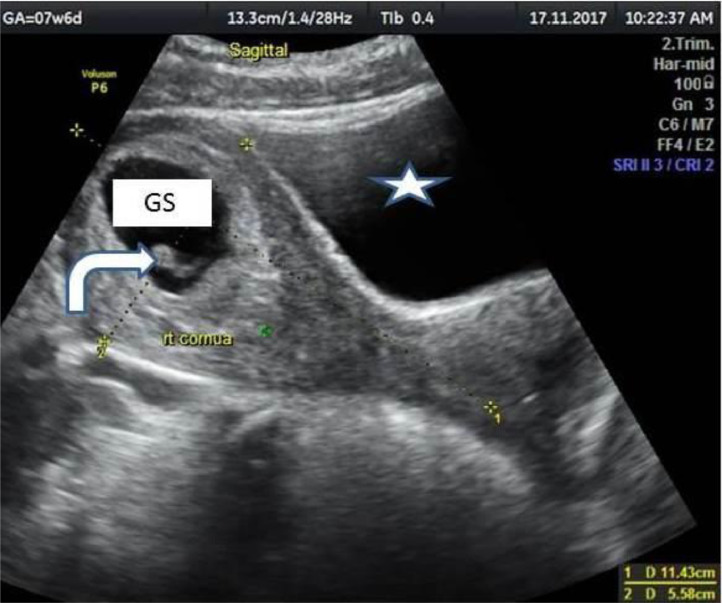

Fig. 2.

Sagittal B-mode ultrasound of the pelvis showing the right uterine horn and cervix measuring 11.43 × 5.58 cm with a gestational sac (GS) its respective fetal pole inside (bent arrow). The myometrial echoes and the urinary bladder (star) are normal.

The obstetric ultrasound revealed 2 uterine horns and 2 cervices (Fig. 1). The right uterine horn was gravid and measured to be 11.4 cm x 5.6 cm. It contained a gestational sac with a fetal pole within it (Fig. 2) that exhibited cardiac activity. The myometrium of the right uterine horn showed uniform and normal myometrial echoes (Fig. 2). The gestational age of the fetal pole was 7 weeks and 6 days. The left uterine horn was empty and measured to be 8.4 × 3.7 cm (Fig. 3). The left horn revealed normal endometrial echoes, however, there was an oval shaped hypoechoic structure that was casting venetian shadows seen in the anterior myometrium near the fundus indicative of a fibroid (Fig. 3). The fibroid measured 1.8 cm x 1.9 cm. There was also an oval shaped, thin-walled anechoic structure seen within the right ovary with posterior acoustic enhancement consistent with a cyst. It measured 4.9 cm x 4.7 cm x 4.7 cm with an estimated volume of 56 mL (Fig. 4). The patient declined to undergo hysterosalpingography (HSG) after delivery of her child.